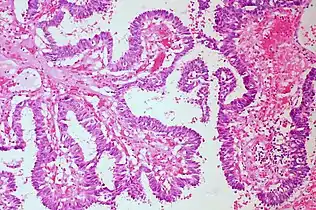

- Papillary: Protuberances of epithelioid cells around fibrovascular cores.

- Micropapillary: Papillary tufts without fibrovascular cores